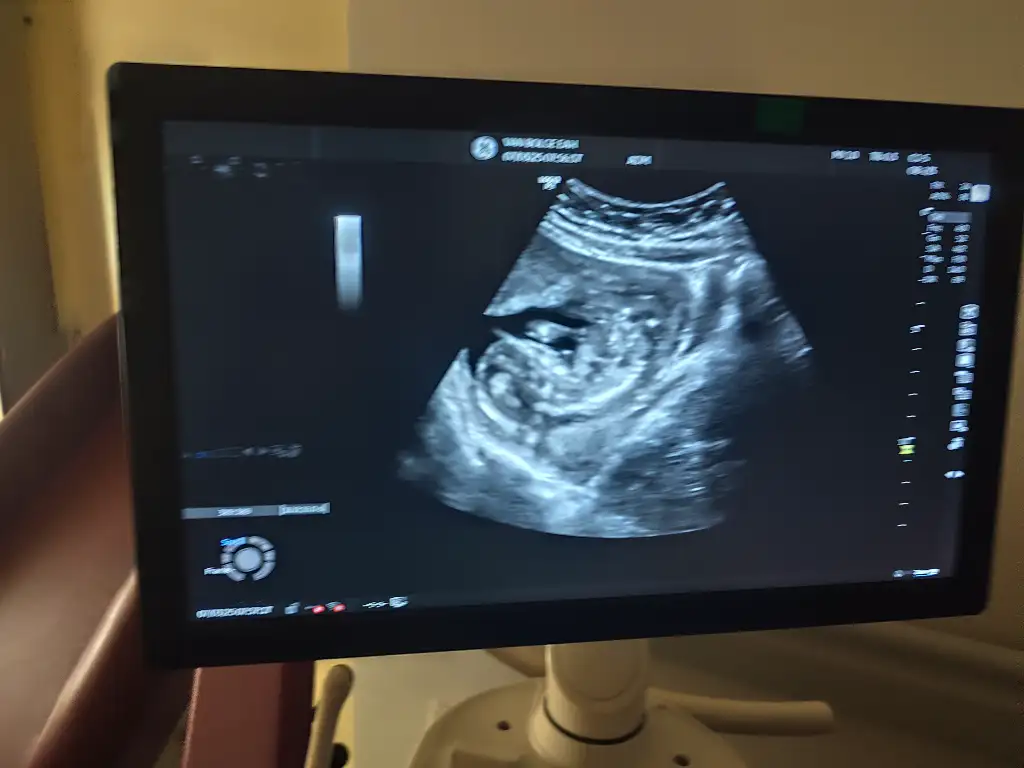

Merhaba biz 11 haftalık olduk şükür, sizde durumlar nedir. Bir de şuan görünüyor mu cinsiyet?Bende pazartesi gideceğim 7 haftalık olacak. Her şeyin yolunda olduğunu duymak nasip olsun inşallah![]()

Güncel ultrasonumuz, 11 haftalık olduk şükür, sizce şuan görünüyor mu cinsiyet belli mi?Vajinal ultrasonla bakıldıysa bebeğiniz kız olabilir![]()